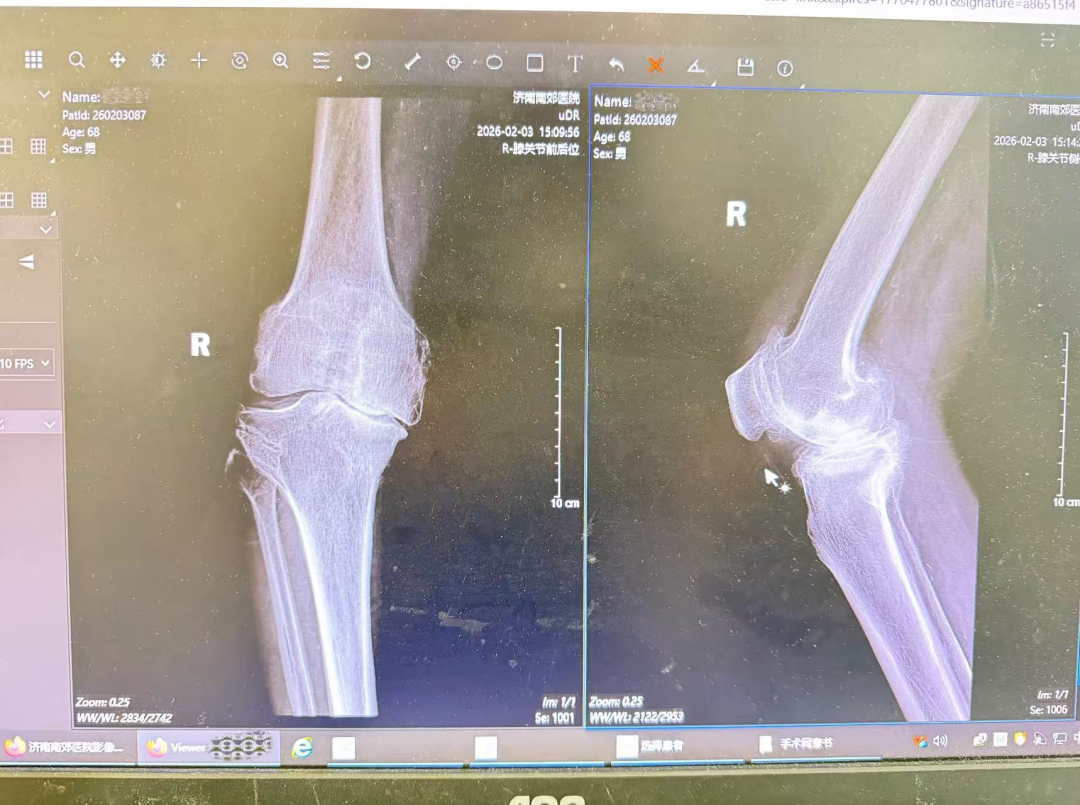

骨二科杨学良主任带领团队分析患者病情,患者病程八年,保守治疗效果差、症状进展,结合各项情况,杨主任判断其双侧膝关节骨性关节病到中晚期,右膝病理改变重致疼痛与功能障碍。团队为患者完善双膝影像学检查明确状况,完成术前评估排查禁忌。